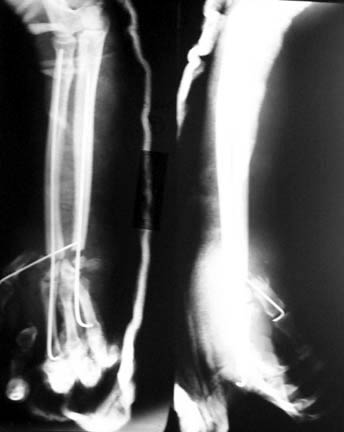

Shortened ulna and stabilised to hand using K wires. First metacarpal axially stabilised.

Primary anastomosis of vessels, tendons and nerves. Volar skin partially primarily closed and rest with a microvascular grascilus free flap to cover dorsolateral aspect. Split skin graft to cover the muscle.

At the moment the hand is vascular and patient okay.